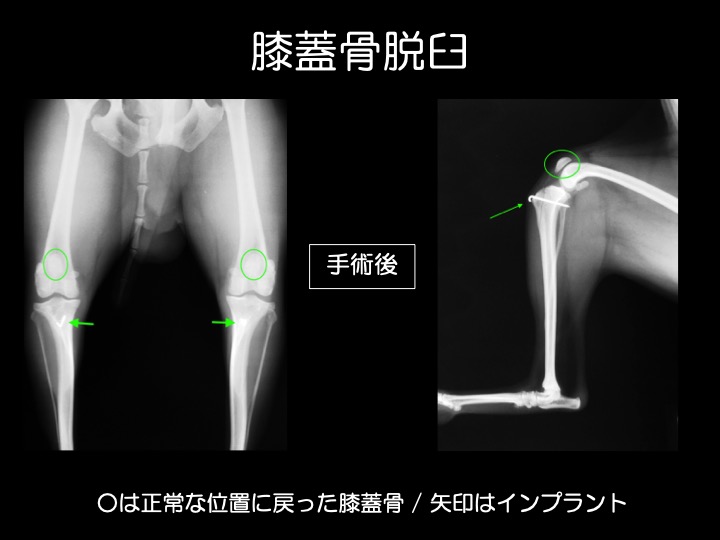

・膝蓋骨脱臼とは、後ろ足の「ひざの皿(膝蓋骨=パテラ)」が大腿骨滑車(皿の収まる溝)から外れる状態をいいます。

・外傷が原因で脱臼することもありますが、多くは先天性で成長期の異常として見つかります。トイプードル、チワワ、 柴犬などに多い疾患です。

・膝蓋骨が脱臼すると、膝をまっすぐに伸ばせなくなるため、ケンケンしたり、突然キャンと泣いて後ろ足を気にする、ガニ股に見える、などの症状がみられます。

・当院では、①明らかな症状がある場合(中等症〜重症)や、②生後6ヶ月未満の若い時期に脱臼が見られる場合(成長に伴い悪化するリスクが高い)に、治療、手術をお勧めしております。